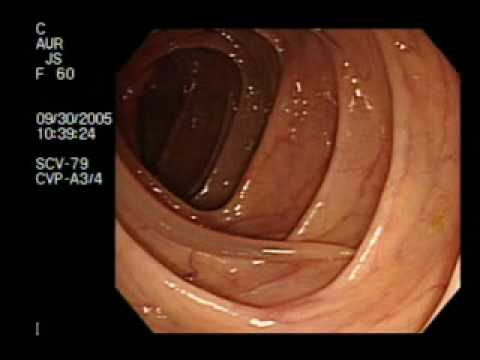

Balon W Żołądku - Kontrola Wagi

Poniższy materiał przedstawia balon w żołądku umieszczony w celu uzyskania właściwej kontroli wagi pacjenta.